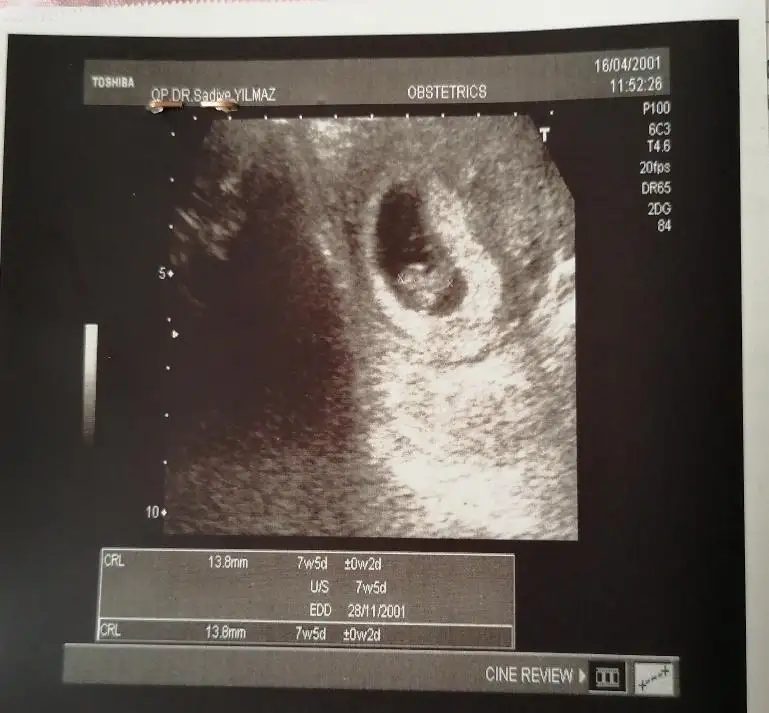

Selam kizlar yil oldu girmeyeli nasilsiniz😍 7 haftalik tahminlerinizi alirim karindan usg sol kesede bekliyorum😘